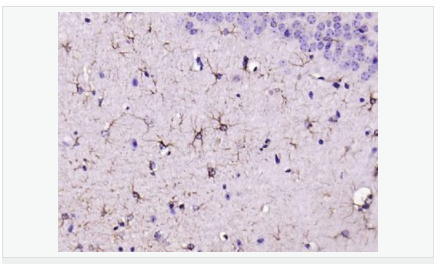

| 產品應用 | WB=1:500-2000 ELISA=1:5000-10000 IHC-P=1:200-1000 IHC-F=1:200-1000 Flow-Cyt=1μg/Test ICC=1:100 IF=1:200-800 (石蠟切片需做抗原修復) not yet tested in other applications. optimal dilutions/concentrations should be determined by the end user. |

| 產品介紹 | This gene encodes one of the major intermediate filament proteins of mature astrocytes. It is used as a marker to distinguish astrocytes from other glial cells during development. Mutations in this gene cause Alexander disease, a rare disorder of astrocytes in the central nervous system. Alternative splicing results in multiple transcript variants encoding distinct isoforms. [provided by RefSeq, Oct 2008] Function: GFAP, a class-III intermediate filament, is a cell-specific marker that, during the development of the central nervous system, distinguishes astrocytes from other glial cells. Subunit: Interacts with SYNM. Isoform 3 interacts with PSEN1 (via N-terminus). Subcellular Location: Cytoplasm. Note=Associated with intermediate filaments. Tissue Specificity: Expressed in cells lacking fibronectin. Post-translational modifications: Phosphorylated by PKN1. DISEASE: Defects in GFAP are a cause of Alexander disease (ALEXD) [MIM:203450]. Alexander disease is a rare disorder of the central nervous system. It is a progressive leukoencephalopathy whose hallmark is the widespread accumulation of Rosenthal fibers which are cytoplasmic inclusions in astrocytes. The most common form affects infants and young children, and is characterized by progressive failure of central myelination, usually leading to death usually within the first decade. Infants with Alexander disease develop a leukoencephalopathy with macrocephaly, seizures, and psychomotor retardation. Patients with juvenile or adult forms typically experience ataxia, bulbar signs and spasticity, and a more slowly progressive course. Similarity: Belongs to the intermediate filament family. SWISS: P14136 Gene ID: 2670 Database links: Entrez Gene: 2670 Human Entrez Gene: 14580 Mouse Omim: 137780 Human SwissProt: P14136 Human SwissProt: P03995 Mouse Important Note: This product as supplied is intended for research use only, not for use in human, therapeutic or diagnostic applications. 星形膠質細胞標志物 (Astrocyte Marker) GFAP是一個56kDa的中間絲蛋白(intermediate filament,IF),在中樞神經系統(tǒng)發(fā)育期是一個特異性的標志物,以區(qū)別星形細胞和其它膠質細胞。GFAP表達在皮層和海馬,急、慢性皮質酮治療時表達減少。 GFAP可以和人、大鼠、小鼠的GFAP反應,在正常和腫瘤性的星形膠質細胞陽性表達,而神經節(jié)細胞、神經元、成纖維細胞、少突膠質細胞和這些細胞來源的腫瘤細胞陰性表達,主要用于星形膠質瘤等中樞神經系統(tǒng)腫瘤的診斷和鑒別診斷,GFAP的缺乏可導致AD病。 |